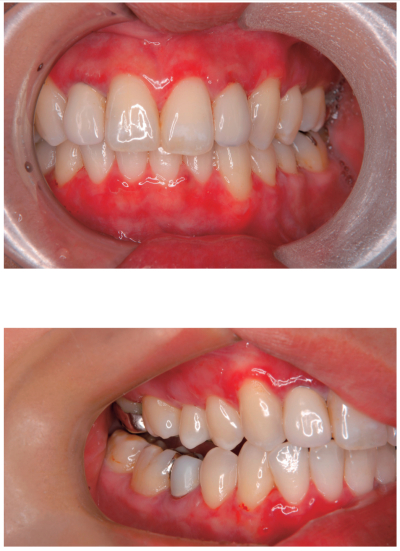

38歳の女性。歯肉の接触痛を主訴として来院した。3か月前から歯肉に水疱ができて、すぐに潰れしみるようになり、次第に口腔内全体がヒリヒリ痛むようになったという。初診時の口腔内写真と生検時のH-E染色病理組織像を別に示す。

BP180 類天疱瘡

デスモグレイン 尋常性天疱瘡